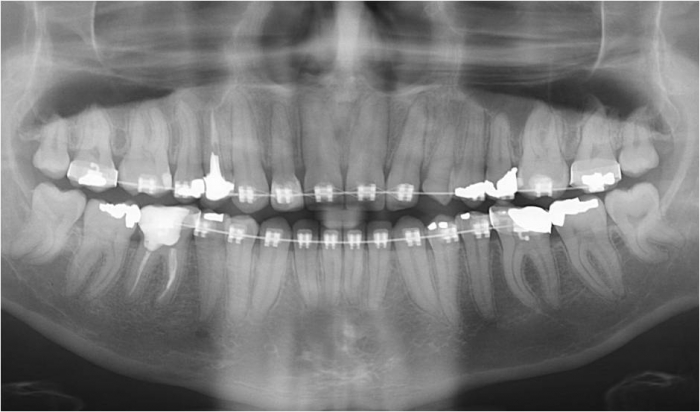

Raio X com raiz do dente 22 distalizada